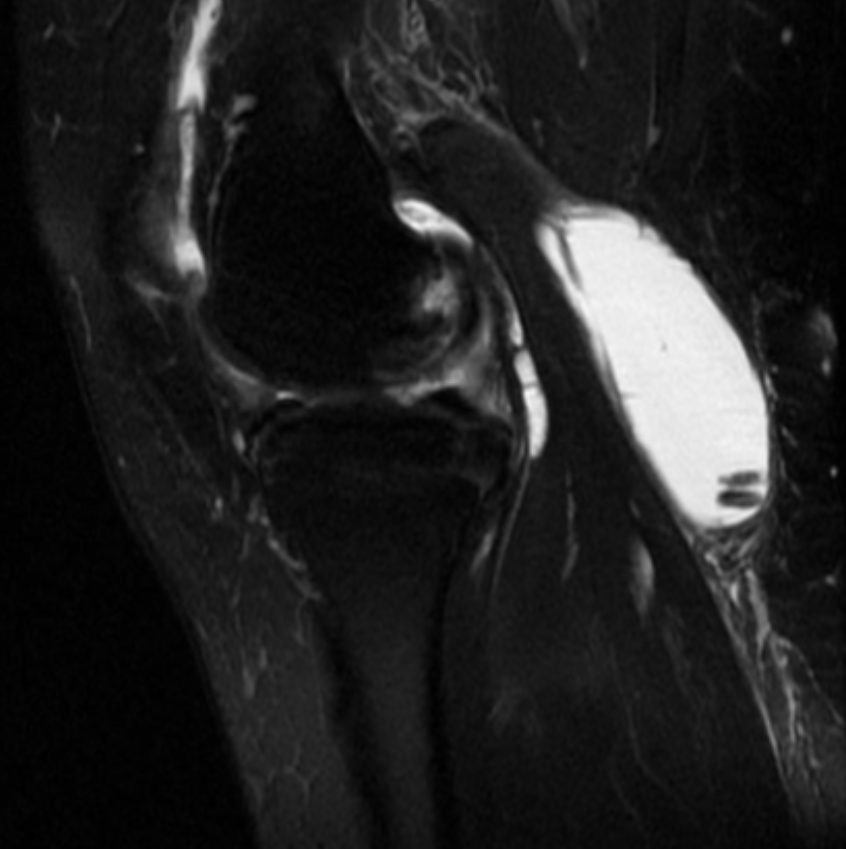

Describe the pathology (Sag T2 FS).

Baker’s cyst